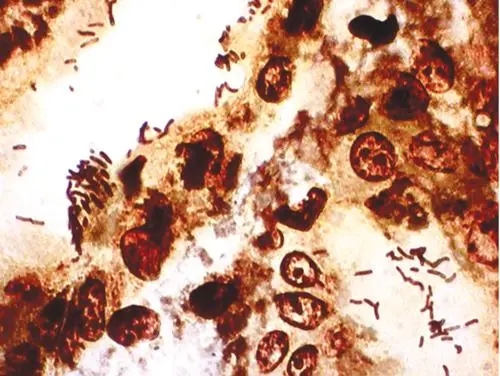

糞腸球菌革蘭氏染色

糞腸球菌革蘭氏染色 當(dāng)前位置:首頁(yè) > 公司產(chǎn)品 > 產(chǎn)品服務(wù) > 瑞果產(chǎn)品展示 > 細(xì)菌